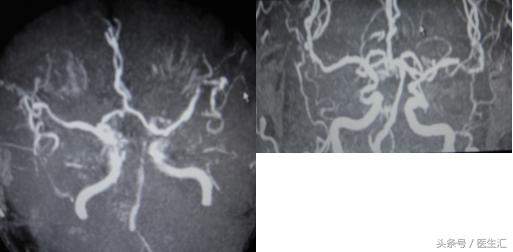

2、头颅MRI、MRA及脑血管三维重建(图12、13、14)

DSA:BA与LVA交界处斑块影,BA远端不显影,从VA缓慢注入rtPA35mg,复查BA、PCA再通(见图20)。但NIHSS评分改善不显著。